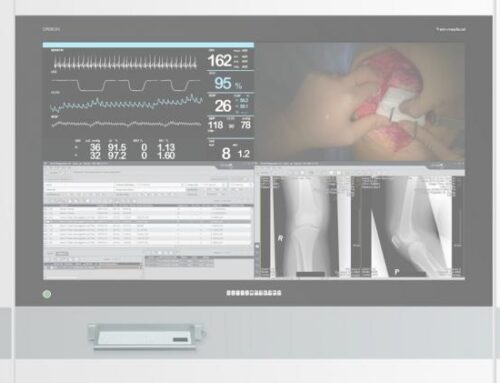

Afficher des images médicales de différentes modalités comme le scanner, la CR/DR, l’IRM, l’échographie ou la mammographie et la pathologie sur un seul écran – c’est ce que souhaitent la plupart des radiologues. En effet, nombre d’entre eux utilisent encore aujourd’hui plusieurs écrans médicaux côte à côte. JVCKENWOOD rend cela superflu avec son nouveau moniteur couleur de 30,9 pouces CL-S1200. L’appareil de 12 mégapixels (4.200 horizontaux et 2.800 verticaux) peut afficher différentes images médicales côte à côte. La disposition des fenêtres peut être choisie librement et le grand écran sans barre centrale crée un environnement confortable pour les diagnostics radiologiques. Avec une luminosité maximale de 1200 cd/m² et un rapport de contraste de 1500:1, il est également adapté à la mammographie.